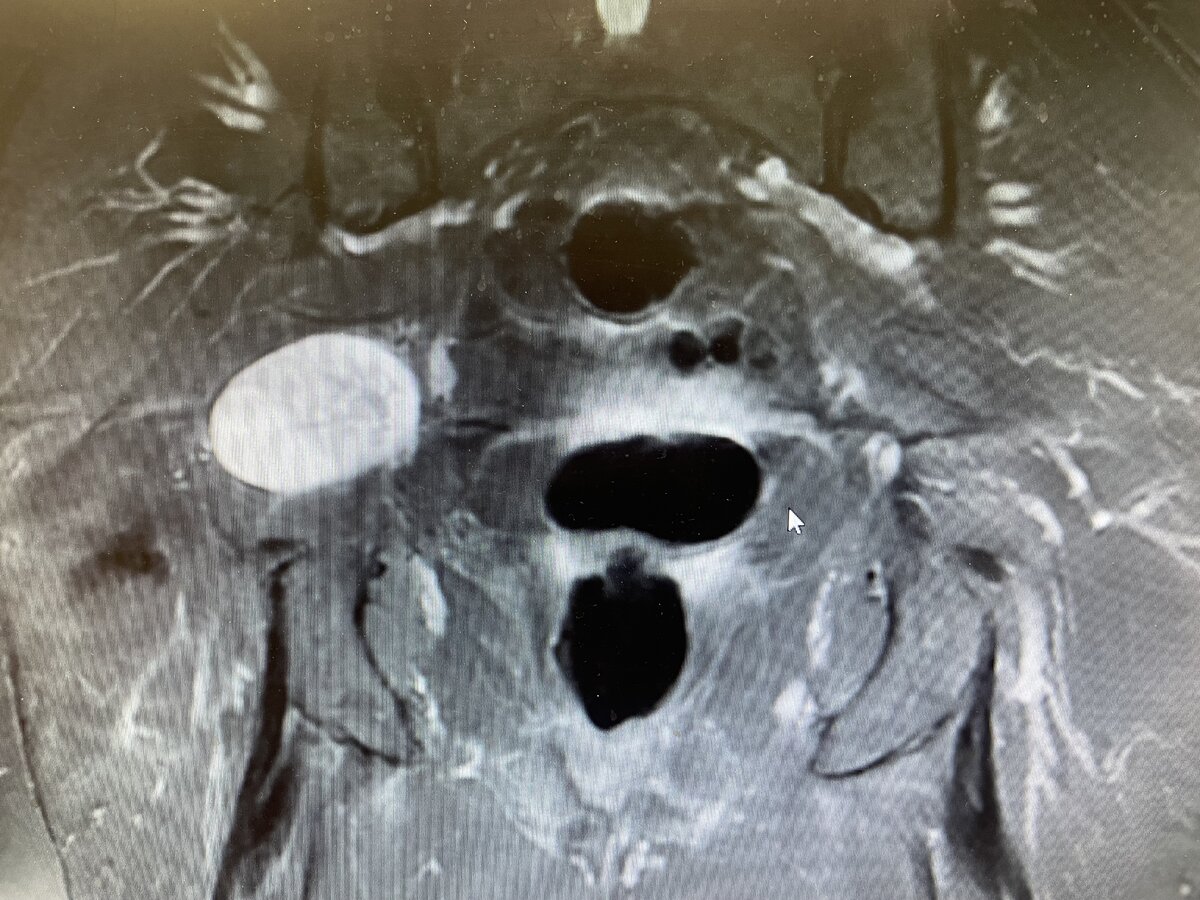

I have a patient coming in with a biopsy proven schwannoma of the greater sciatic foramen. It measures 4.7 x 3.6 x 3.2 cm and is symptomatic. How would you treat something of this size/location assuming surgery is not an option.

Pt is in her mid 70's with an ECOG of 0 to 1. Pt presented with issues of pain presumably due to the mass but otherwise neurologically intact with no weakness.